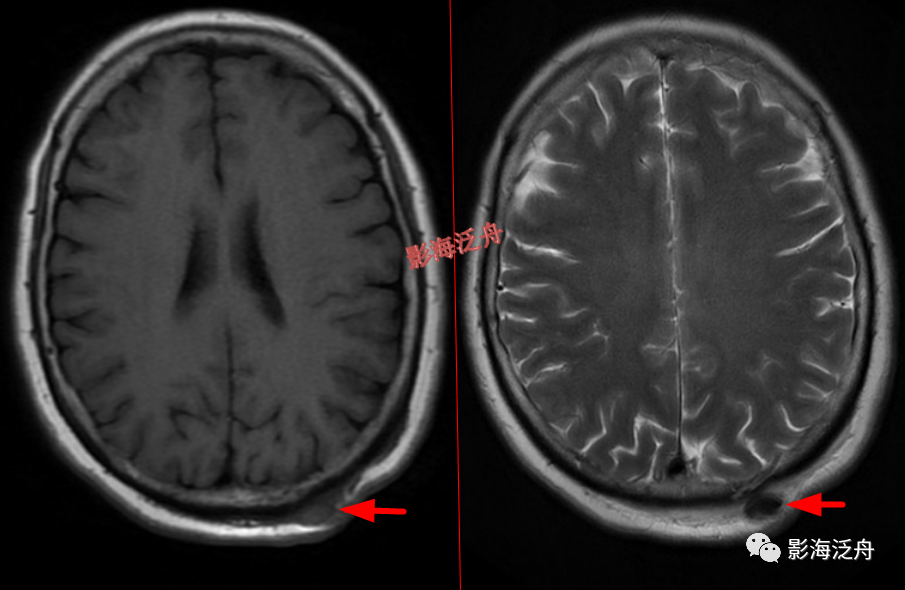

头皮下病变

头皮下血管瘤以及皮脂腺瘤是非常常见的,单也很容易漏诊,尽管临床意义不大,但还是应当避免漏诊,毕竟现在的大家的处境一言难尽~

右侧额部头皮下血管瘤。患者为11岁女性,是本病的高发年龄段,这个结节要是漏诊,恐怕会有麻烦。

头皮血肿(急性期),病灶在T1WI及T2WI上均呈低信号。